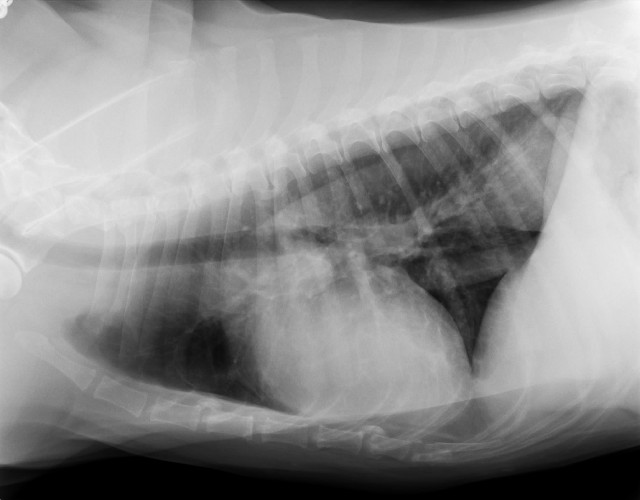

●レントゲンも3枚(胸・腰)撮りました。

うちの獣医さん、この秋にレントゲンをデジタル化したの。

だから、画像をCDに落としてもらえるようになったんだよヽ(*'0'*)ツ

キレイだからべべちゃんの“ヌード”3枚見てね。

診断としては、内臓関係は肺以外みんなOK(^^)v

肺は、べべは6歳半でうちに帰ってきた時にすでにフィラリアに罹っていて、肺に成虫が達していて、それを治療した残骸がある?し、フィラリアの影響か?肺のあちこちが石灰化してるの(前から)

背骨は変形性脊椎症であちこちブリッジにはなっているけど、これからも関節サプリ/アースリスージゴールドやマッサージやレーザーで手当てしてあげながら上手く着きあっていけば大丈夫♪